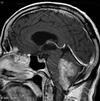

There is a mass in the left hemisphere (A) surrounded by an extensive area of low density (B) which represents oedema. There is midline shift (C) and compartmental hydrocephalus (demonstrated by the enlarged lateral ventricles on the right (D) due to compression of the ventricular system at the foramen of Monro. There is herniation of the uncus of the left temporal lobe seen on the lower slice (E).

The mass exhibits ring enhancement. The differential diagnosis is between a highgrade glioma, an abscess, and metastasis. In the absence of raised infective markers, a tumour is more likely